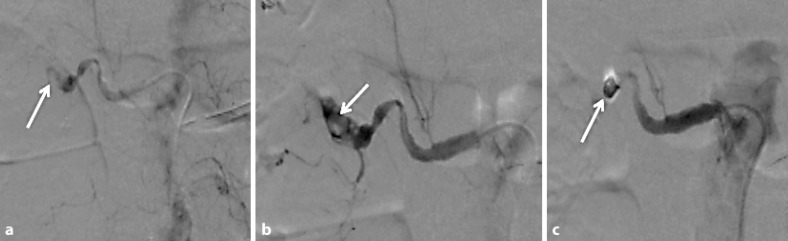

Dialysis patients have a tendency to bleed, and clinicians sometimes encounter cases with a significant amount of spontaneous hemorrhage. We herein report two cases of spontaneous renal hemorrhage in hemodialysis patients. CASE 1: A 70-year-old male who had received hemodialysis for 8 years presented with right abdominal pain. He had a history of renal failure due to diabetes mellitus. CT showed a right perirenal hemorrhage. Angiography revealed a right renal artery hemorrhage, and catheter embolization was performed. CASE 2: A 76-year-old male who had undergone 7 years of continuous ambulatory peritoneal dialysis and 1 year of hemodialysis presented with right abdominal pain. He had a history of renal failure due to IgA nephropathy. CT showed a right perirenal hemorrhage. He received a blood transfusion and was put on absolute bed rest. At 2 days after admission, his anemia was found to have improved.